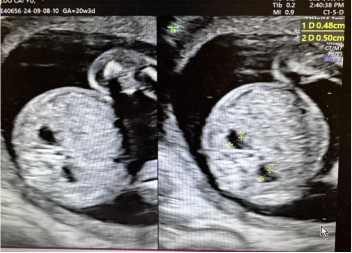

胎儿侧脑室宽度应<10 mm,当10㎜≤侧脑室宽度<15 mm时为轻度侧脑室增宽(可一侧或双侧)②。轻度侧脑室增宽与染色体异常、遗传综合征、脑发育异常、宫内感染(巨细胞病毒、弓形虫感染等)、颅内出血等相关。侧脑室宽度在10-12 mm的胎儿大部分预后良好,13㎜≤侧脑室宽度<15 mm的胎儿,其不良结局的风险增高。超声发现轻度侧脑室增宽,或侧脑室进行性增宽,需进行系统超声检查,排查胎儿的结构畸形, 胎儿非孤立性轻度侧脑室增宽时,建议行介入性产前诊断以及颅脑MRI,排除胎儿中枢神经系统异常可能。胎儿孤立性轻度侧脑室增宽时,建议定期产检并随访超声,动态观察,必要时行介入性产前诊断以及胎儿颅脑MRI。